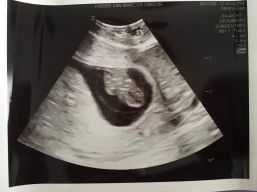

It was so fun to meet up at the Post Office with Mitch and Sarah Peters and daugher, Giana. They have enjoyed their time together so much with the adventure of a snow storm and her home-schooling and all the fun of quarantining on the Mountain. Giana has been an ‘only child’ and now that status is expiring. Number Two is on the way in November!